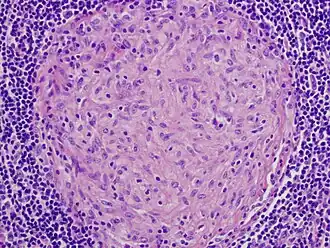

Photo (microscopie) d'un granulome (sans nécrose) vu en coupe, provenant d'un ganglion d'un patient infecté par Mycobacterium avium. L'échantillon a été coloré avec deux colorants standard (hématoxyline : bleu - éosine : rose)